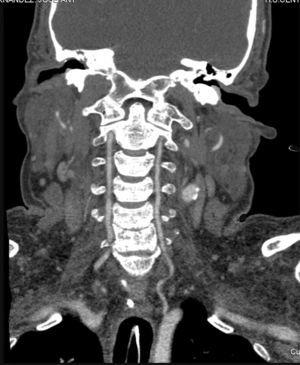

La angiografía computarizada constató en todos los casos la detención del contraste al nivel del agujero magno sin visualizarse contraste en arterias vertebrales intracraneales. Al estudiar la circulación anterior se visualiza un afilamiento progresivo de las arterias carótidas internas en el cuello, comprobándose que el contraste se detiene en la porción petrosa carotídea, y demostrándose la ausencia de relleno de las arterias carótidas internas intracraneales. Se observa relleno de contraste en las diferentes ramas de las arterias carótidas externas (figs. 1-4).

Figura 1. Angio-tomografía computarizada que demuestra la ausencia de circulación intracraneal. Las flechas finas indican las ramas arteriales de la arteria carótida externa y la flecha gruesa la craneotomía.

Figura 4. Reconstrucción multiplanar en proyección coronal, que demuestra relleno de contraste de las arterias vertebrales a nivel extracraneal con ausencia de flujo en la fosa posterior.